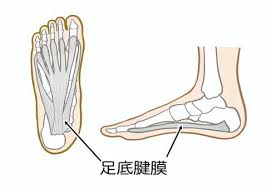

足底腱膜炎とは

足の裏にある腱膜という組織が炎症を起こすことで、かかとから土踏まずにかけて痛みを感じる疾患です。